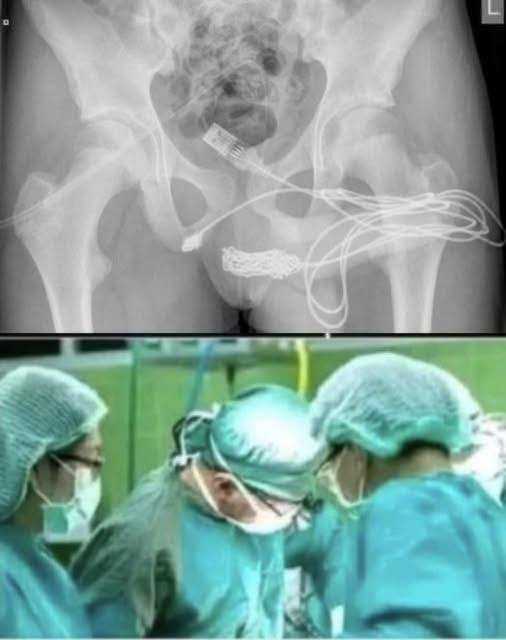

shocking case has gone viral on social media after a young girl had to be rushed to the hospital for a bizarre and dangerous act. According to reports, the teenager inserted a pen into her private parts, which led to severe internal injuries and complications.

Doctors performed an emergency surgery to remove the object and stabilize her condition. Medical experts are now warning young people not to experiment with foreign objects, as it can lead to life-threatening infections or permanent damage.